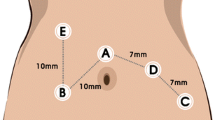

Optimization of the suprapubic surgical approach

Exploration of new surgical approaches, such as the optimization of the suprapubic method, is of clinical significance. A convenient surgical approach can increase the fluency of the operation and reduce collision of the robotic arms. The suprapubic surgical approach means colonic resection performed with horizontal linear placement of ports in the suprapubic area, especially applied in the robotic right hemicolectomy (Fig. 2). Hamilton et al. [37] reviewed technical and perioperative outcomes using the dVXi and dVSi systems with suprapubic port placement (SPPP) or traditional port placement (TPP) in 138 patients who underwent totally robotic right hemicolectomy (RRHC). The authors reported that SPPP had more advantages than TPP, with less console time and shorter hospital stay. Yeo et al. [38] developed a potentially universal SPPP strategy for robotic colectomy with complete mesocolic excision (CME) and central vascular ligation using the dVXi robotic system from cadaveric models. Lee et al. [39], from Korea, and Schulte Am Esch et al. [40], from Germany, separately described robotic right hemicolectomy using the suprapubic access strategy, and the perioperative effects were relatively satisfactory. The above studies reported optimistic short-term effects, and optimization of the suprapubic surgical approach may be widely used in the future when application conditions and long-term efficacy are further clarified.